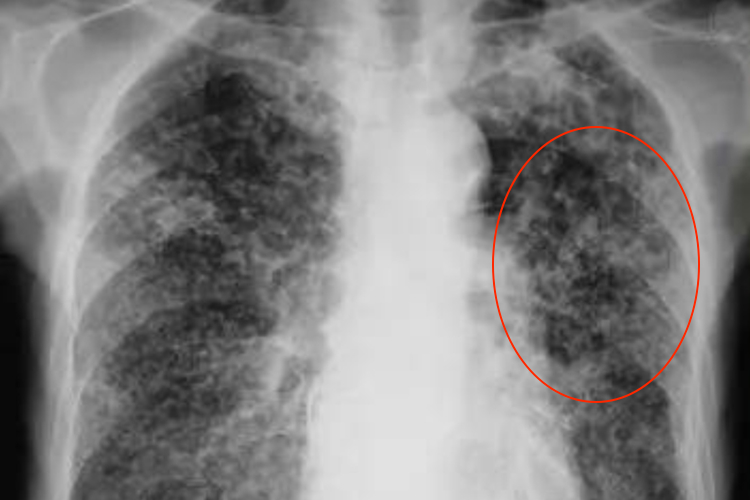

浸润型肺结核:表现为小片状或斑点状阴影,可融合和形成空洞。

结核球:表现为球内有钙化灶或液化坏死形成空洞,同时多数有卫星灶,直径2-4cm,多小于3cm。